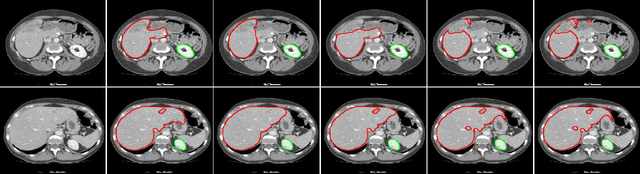

Abstract:Exploiting more information from ground truth (GT) images now is a new research direction for further improving CNN's performance in CT image segmentation. Previous methods focus on devising the loss function for fulfilling such a purpose. However, it is rather difficult to devise a general and optimization-friendly loss function. We here present a novel and practical method that exploits GT images beyond the loss function. Our insight is that feature maps of two CNNs trained respectively on GT and CT images should be similar on some metric space, because they both are used to describe the same objects for the same purpose. We hence exploit GT images by enforcing such two CNNs' feature maps to be consistent. We assess the proposed method on two data sets, and compare its performance to several competitive methods. Extensive experimental results show that the proposed method is effective, outperforming all the compared methods.